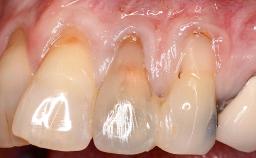

A 30-year-old woman was referred by her general dentist for evaluation of an esthetic complication related to previous implant treatment for congenitally missing maxillary lateral incisors. The patient’s chief complaint was the inadequate esthetic appearance of her smile. The case demonstrates the use of a combined approach to achieve optimal results. Two different flap designs - a tunnel technique and a coronally advanced flap - are employed based on the surgical objectives for the affected site.